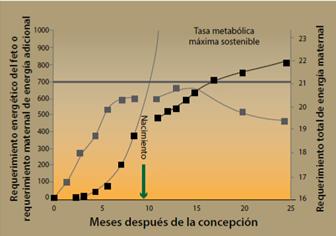

Varias evidencias del dilema obstétrico indican que al nacimiento puede haber un conflicto entre la salida de una cabeza grande y el estrecho diámetro del canal pélvico, que se resolvió haciendo que el feto salga a una edad en la que todavía es inmaduro. Sin embargo, algunas inconsistencias entre esos datos han llevado a la proposición de otra hipótesis que parece explicar igualmente bien la necesidad del nacimiento de un feto prematuro. Esta se denomina EGG (siglas en inglés de “energética de la gestación y el crecimiento”).23

Durante el nacimiento, 2 de las características típicas del género humano, un cerebro grande y la bipedalidad, parecen estar una contra la otra. El cerebro grande y la cabeza grande que lo contiene son difíciles de empujar a través del canal pélvico, lo que requeriría una pelvis más ancha, aunque eso comprometería el bipedalismo. Se ha dicho que la manera como la evolución solucionó ese problema, que se conoce como el dilema obstétrico, fue acortando la duración del embarazo, de manera que los fetos nacen antes de que la cabeza sea demasiado grande y, como resultado, comparados con otros primates los bebés humanos son inmaduros en términos de su capacidad motora y cognitiva.

En forma tradicional todos esos problemas en la evolución humana (bipedalismo, nacimiento difícil, pelvis femenina ancha, cerebro grande y neonatos relativamente inmaduros) han sido unidos en el dilema obstétrico, pero las evidencias no son tantas como uno esperaría. El primer problema es que no hay evidencias que demuestren claramente que una cadera suficientemente grande para que un bebé nazca más desarrollado es en detrimento de la marcha bípeda. En cambio, un trabajo de Warrener24 en relación a cómo afecta la locomoción el ancho de la cadera, parece demostrar que no hay una correlación entre una cadera ancha y una menor economía durante la marcha.

Igualmente, la idea de que el embarazo humano es corto comparado con el de otros primates y mamíferos no parece tener muchas evidencias. En cambio, parece que a considerar por el tamaño corporal de la madre, el embarazo humano es un poco más largo que el esperado comparado con otros primates. Igualmente, los bebés son un poco más grandes de lo esperado, no menores, y aunque se comportan como tales, no nacen más temprano. Más aún, para los mamíferos en general, incluyendo a los humanos, la longitud del embarazo y el tamaño del producto tienen una buena correlación con la tasa metabólica.

Todos esos resultados llevaron al desarrollo de una nueva hipótesis para explicar la temporalidad del nacimiento humano, que fue llamada EGG. Esta hipótesis propone que los bebés nacen cuando la madre ya no puede poner más energía en el embarazo y el crecimiento fetal, de manera que la limitación principal en la longitud del embarazo es la energía de la madre.

Nuestros cuerpos tienen un límite en la cantidad de calorías que pueden quemar en un día, y durante el embarazo las mujeres se acercan a ese límite y dan a luz poco antes de llegar a él. Esos límites metabólicos también explican por qué los bebés humanos son tan inútiles comparados con los bebes de primates como chimpancés, que empiezan a gatear en un mes, mientras los humanos lo hacen hasta aproximadamente los siete meses. Para un humano el dar a luz a un bebé con el mismo nivel de desarrollo de un chimpancé requeriría un embarazo de 16 meses y eso colocaría a las madres más allá de sus límites energéticos. De hecho, parece que solamente un mes más de embarazo hace que las madres entren en la zona de peligro metabólico. Por supuesto, la EGG daría otra forma al dilema obstétrico, ya que no sería el tamaño ni la forma de la pelvis femenina la limitación para el nacimiento de un bebé con una cabeza capaz de contener un cerebro grande.

La figura 14 muestra un diagrama que intenta explicar las diferencias entre las 2 hipótesis que resuelven el dilema obstétrico y aquella basada en la energía de la madre se explica con detalle en la figura 15, donde se ve que la demanda de energía fetal (círculos negros, kcal/día) aumenta exponencialmente durante la gestación. El gasto en energía materna (cuadros grises) se eleva durante los primeros 2 trimestres, llegando a un tope metabólico en el tercero, conforme el requerimiento de energía total se acerca a 2.0 × tasa metabólica basal (BMR, por sus siglas en inglés, basic metabolic rate). Los requerimientos en energía fetal proyectados para un crecimiento más allá de 9 meses (línea punteada) exceden rápidamente las tasas metabólicas máximas sostenibles por las madres humanas. Después del nacimiento (flecha) las demandas energéticas del feto aumentan más lentamente y los requerimiento maternos de energía no exceden 2.1 × BMR. El gasto en energía materna requerido para un desarrollo fetal similar al del chimpancé recién nacido (infante de 7 meses, símbolos con asterisco) implicaría requerimientos en energía maternal mayores de 2.1 × BMR25-27.

Figura 14 Diagramas de las hipótesis del dilema metabólico y de la energética de la gestación y el crecimiento (EGG).